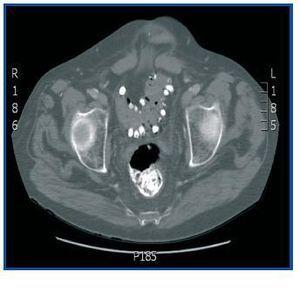

Dear Editor, Lanthanum carbonate is a calcium and aluminium-free phosphorus binder that has recently come to market in Spain. It is a heavy, non-toxic metal that is not absorbed by the intestine. The substance’s package leaflet in our country does not allude to the phenomenon of its appearance in radiology images. This is not the case in the USA’s version, which states that “radio-opaque images may appear in abdominal radiographies of patients who consume lanthanum”.1 The most commonly reported adverse reactions were gastrointestinal, but the clinical trials did not include patients with intestinal obstructions or inflammatory intestinal disease.2 We present the case of a 58-year old man with pan-colonic diverticulosis and frequent diverticulitis episodes with CKD secondary to diabetic nephropathy who began a periodic haemodialysis programme in April 2001. He was admitted in July 2008 for fever and abdominal pain. An emergency abdominal CT ruled out signs of diverticulitis, but the radiologist reported “remnants of contrast in the entire colon and terminal ileum” (figure 1), which was confirmed by a simple abdominal x-ray (figure 2). Our patient had not received any radiological contrast at any time, but he had been receiving treatment with 3000mg lanthanum carbonate daily for severe hyperphosphataemia since February of that year, with excellent lab results and good clinical tolerance up to that moment. The final diagnosis was sepsis due to Enterococo avium, most likely of intestinal origin. Since there were no other findings in the imaging tests that could explain the abdominal pain, lanthanum treatment was discontinued, after which the patient remained asymptomatic. With a view to studying the findings, a simple abdominal radiograph was taken in another patient receiving the same dose of that metal and who had not had any digestive symptoms. The deposit was also observed throughout the contour of the colon, but showed a different radiological pattern (figure 3). References in the literature describing this phenomenon are scarce and contain various explanations. According to our research, the first radiological image attributed to lanthanum consumption was shown by Cerny and Kunzendorf3 in 2006. In this case, the drug was discontinued because after seeing the radiography, doctors felt that the patient’s abdominal pain could be related with the lanthanum. Other cases were subsequently reported.4 David et al.5 interpreted the radiograph as an intestinal deposit of calcium phosphate stones that prove lanthanum’s effectiveness as a binder, and even suggest that such an image could be used as a test of therapeutic compliance. That theory is refuted by Pafcugova et al.,6 who showed that the tablets themselves inside a vial are radio-opaque, in absence of calcium or phosphorus. However, given our limited experience with the use of this drug, particularly in Spain, it is still not clear what the radiographical distribution pattern is in the abdomen, or whether it can be observed in all patients receiving this medication. Vrigneaud et al.7 studied 13 patients treated with lanthanum. In six, the abdominal radiograph is completely normal, while in the rest, the radioopaque deposit may be observed. However, in contrast with the habitual images with opaque areas smaller than one centimetre distributed regularly throughout the contour of the colon, we found two cases in which the areas were larger and irregularly distributed along the digestive tract. These were in one patient who did not chew the tablets correctly, and another patient with colonic diverticulosis whose profile suggests the material was deposited in the diverticuli, as with the present case. Our conclusion is that although little data exists about the radiological behaviour of intestinal lanthanum carbonate deposits, it is necessary to know that it is radio-opaque. Furthermore, it is likely that the drug should be used cautiously in patients with intestinal diseases. In addition, we do not know its elimination time, which is crucial information when it comes to performing other imaging studies without interferences. And lastly, we believe that all of the above should be included in the drug’s technical leaflet printed in Spain.

Figure 1. Abdominal CT without contrast showing the lanthanum carbonate deposit in the sigmoid colon diverticuli and rectum.